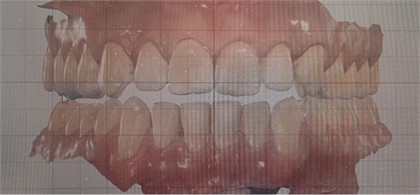

A 36-year-old man with unilateral crossbite (Fig. 1) and facial asymmetry in addition to joint discomfort underwent dental and osteopathic evaluation. The determination of a treatment plan and selection of medical approaches were based on a comprehensive examination, including functional evaluations, analysis of plaster models of dental arches, cone beam computed tomography (CBCT), and also manual and visual testing using the “from bite to foot” method [5], created by the first author (appendix). After diagnosis, the patient underwent to an osteopathic manual therapy to liberate fascia, associated to the use of the CPB [6] to posture the mandible in a correct position and guide the tongue for the palate (Fig. 2). The CPB was constructed to maintain the mandible in a manipulated position avoiding dental interferences. The Coffin was constructed with the curvature to the front and anteriorized to allow bigger stimulation of the premolar and canine area. The appliance was used 12 hours a day, always including sleeping time and the activation was done every 15 days.

Fig. 1Beginning pictures: a) inclined view to show the negative overjet on posterior right, characterizing unilateral crossbite and generating midline deviation to the right; b) frontal view showing that in the manipulated position, avoiding dental interferences, the midline is almost centralized indicating that crossbite and deviation were positional due to narrowing of the palate requiring remodeling on both sides

a)

b)